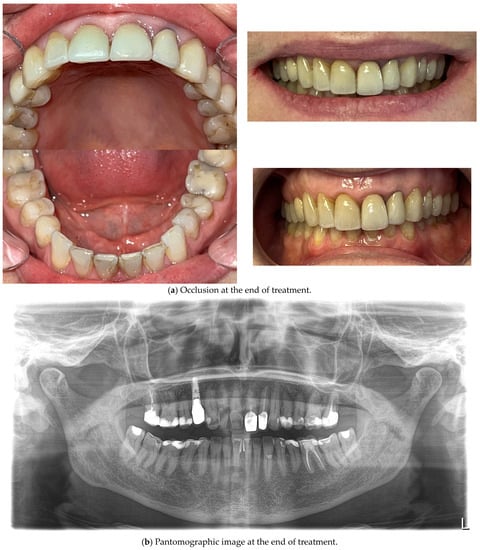

The final treatment effect is shown in Figure 10a,b.

Figure 10.

The outcome of the clear aligner treatment in photos, scans and X-rays.

Periodontal status and oral hygiene were regularly monitored during treatment. Professional teeth cleaning was performed every 3 months. After obtaining the correct position of the teeth, thermoformable splint retention treatment was applied and the occlusion was rechecked for possible traumatic nodes. There were improvements in tooth stabilization (mobility of the first degree on the Miller scale) and the position of the connective tissue attachment on the labial surface—CAL—2 mm and PPD also 2 mm. The patient was not referred for re-endodontic treatment of the tooth since the previous root canal treatment was surely carried out according to the most modern standards at that time—under a microscope, filled with liquid gutta-percha—the gaps in the canal visible on the X-ray are not due to incomplete filling—the canal was obliterated, probably due to tooth trauma in childhood and the slow death of the pulp inside the tooth.